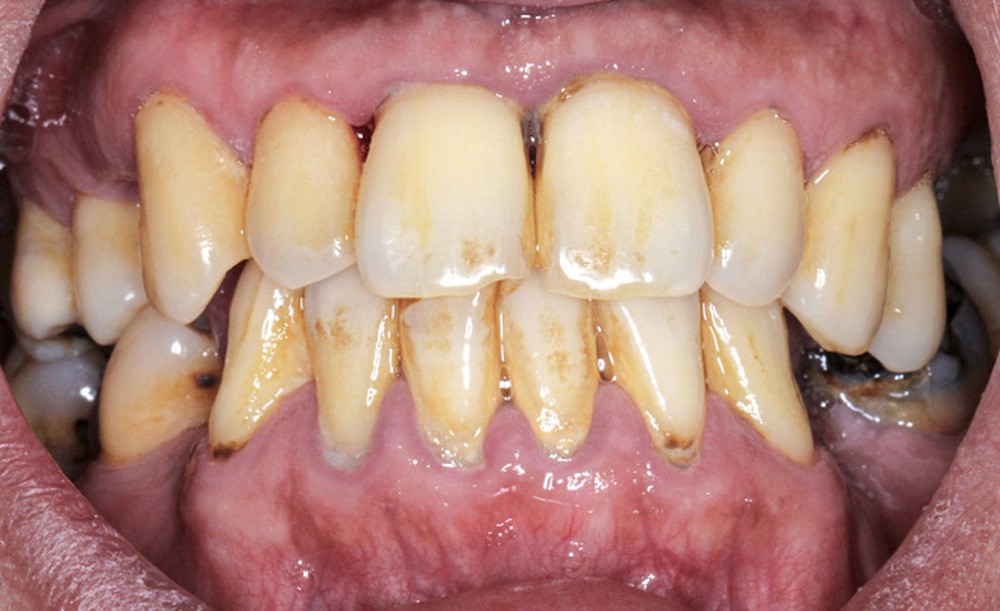

L’obésité, définie par un indice de masse corporelle (IMC) ≥ 30 kg/m2, est une maladie inflammatoire chronique complexe et multifactorielle caractérisée par un dépôt excessif de graisse dans le tissu adipeux. Selon l’OMS, depuis 1975, le nombre de cas d’obésité a presque triplé à l’échelle planétaire [1]. En 2020, près d’un Français sur deux était en surpoids, tandis que 17 % étaient obèses [2]. Or l’obésité est responsable d’une haute mortalité à l’échelle mondiale et est un facteur de risque majeur pour de nombreuses maladies, dont les maladies cardiovasculaires, le diabète de type 2 et certains cancers [1]. Son impact sur la santé des populations et son coût économique et social sont donc considérables. Ces deux dernières décennies, de nombreuses études ont montré que l’obésité pouvait aussi être incriminée dans la détérioration de la santé bucco-dentaire [3] (fig. 1 à 7).